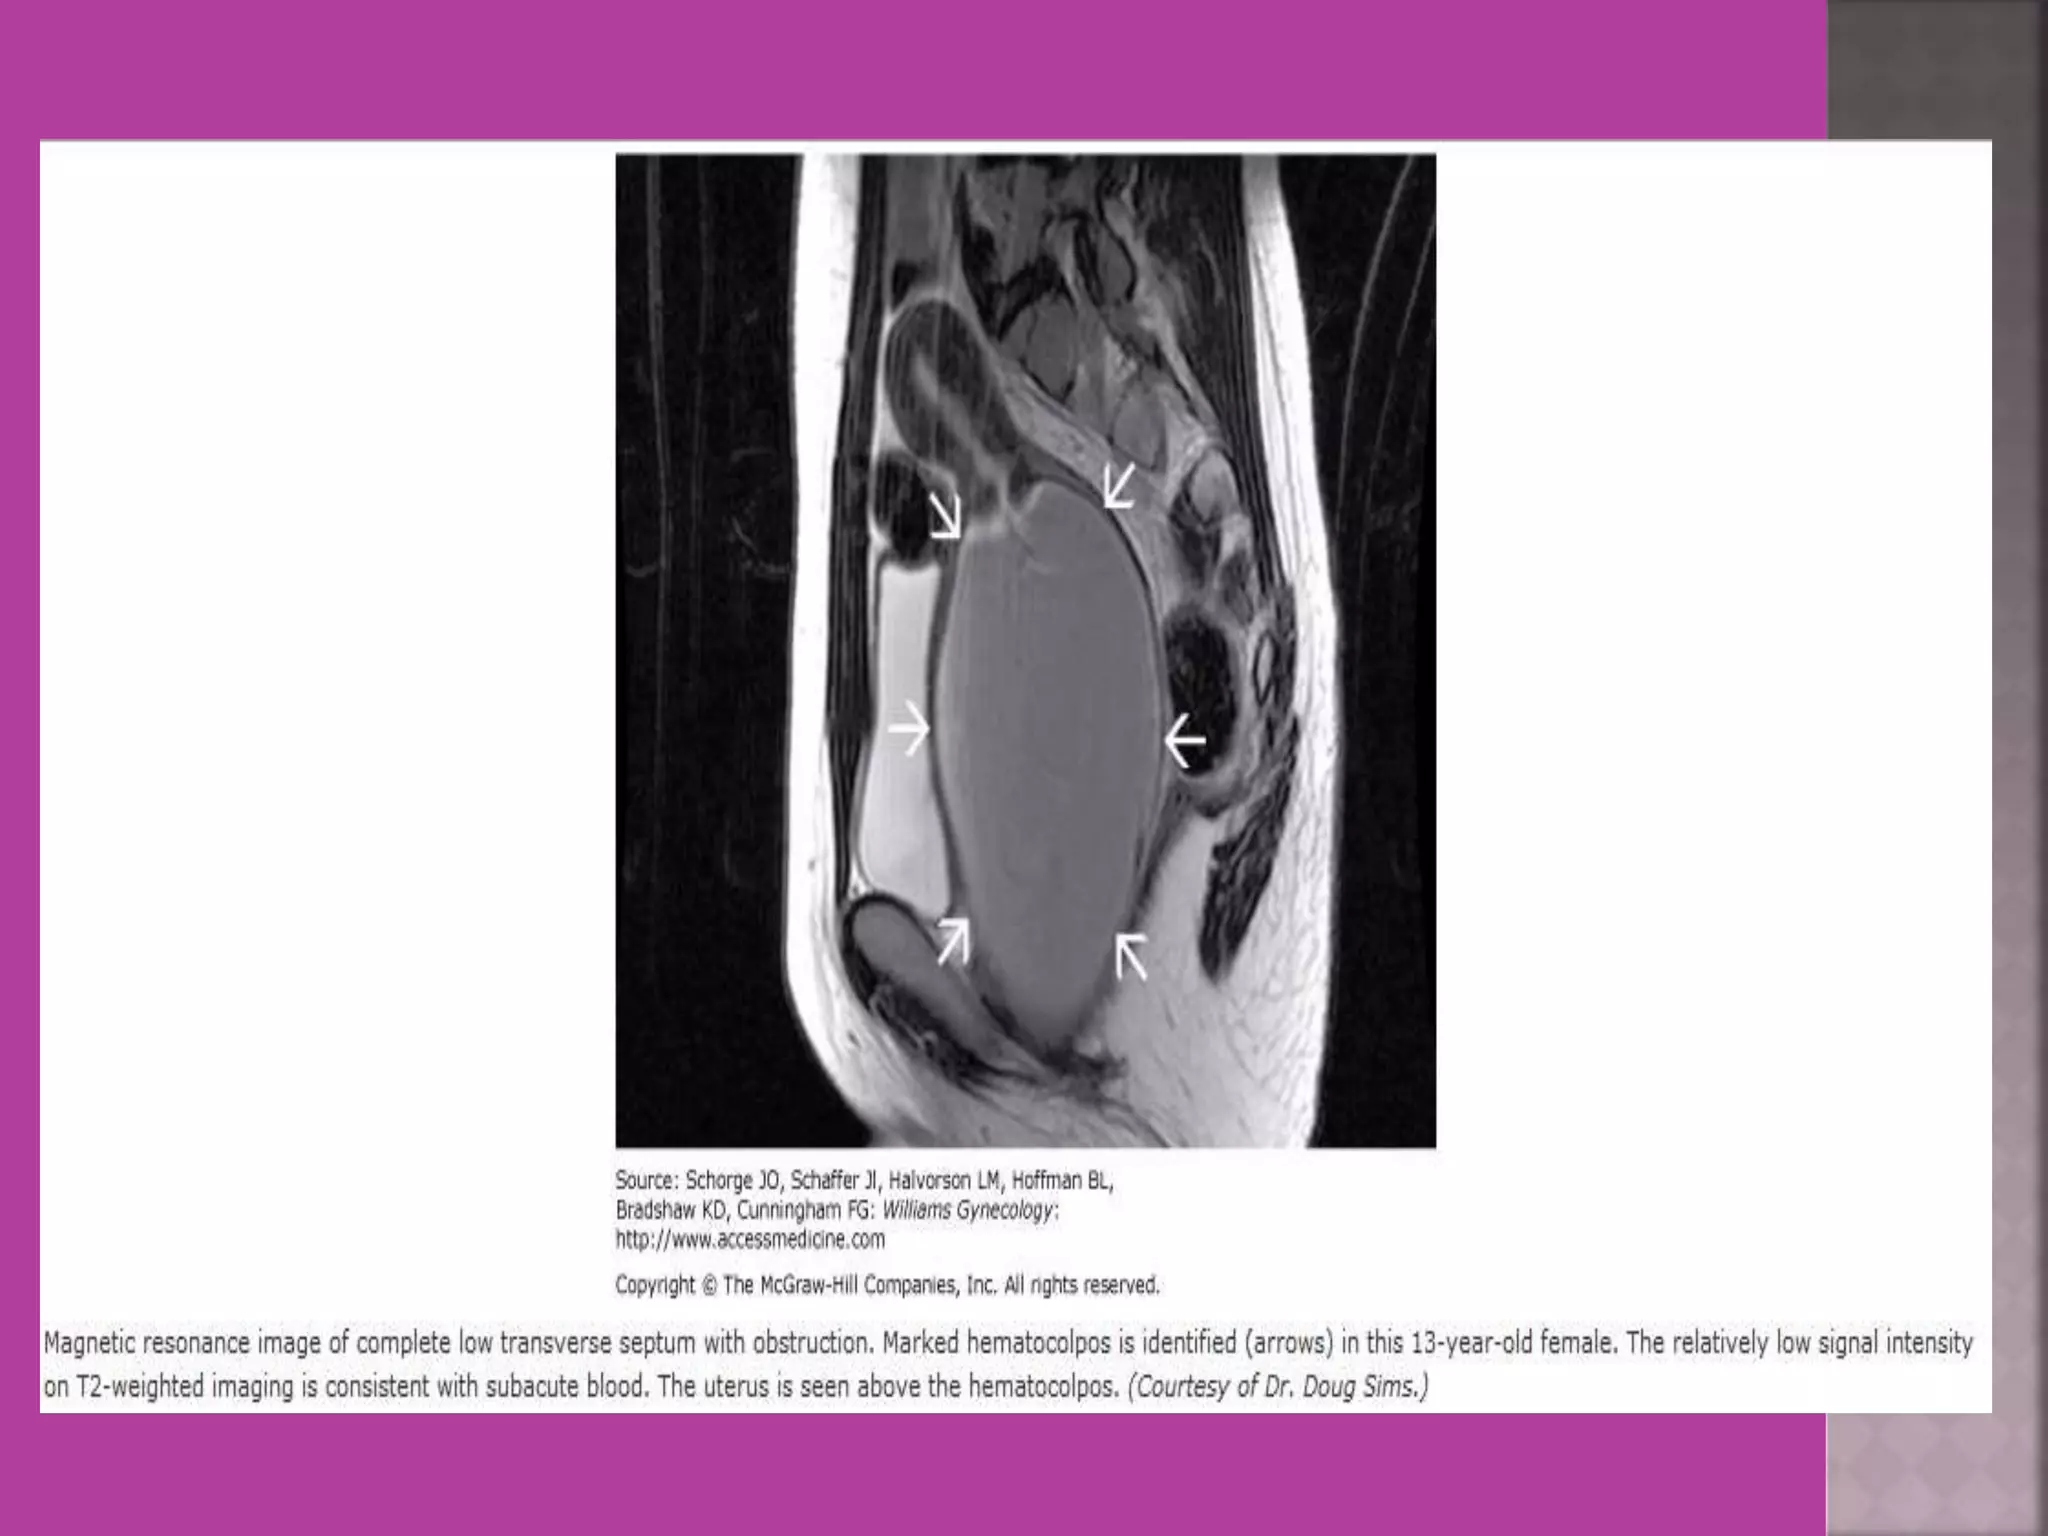

 Congenital uterovaginal anomalies—

bicornuate, septate,subseptate ,

unicornuate, didelphys ,rudimentary horn

and vaginal atrasia etc